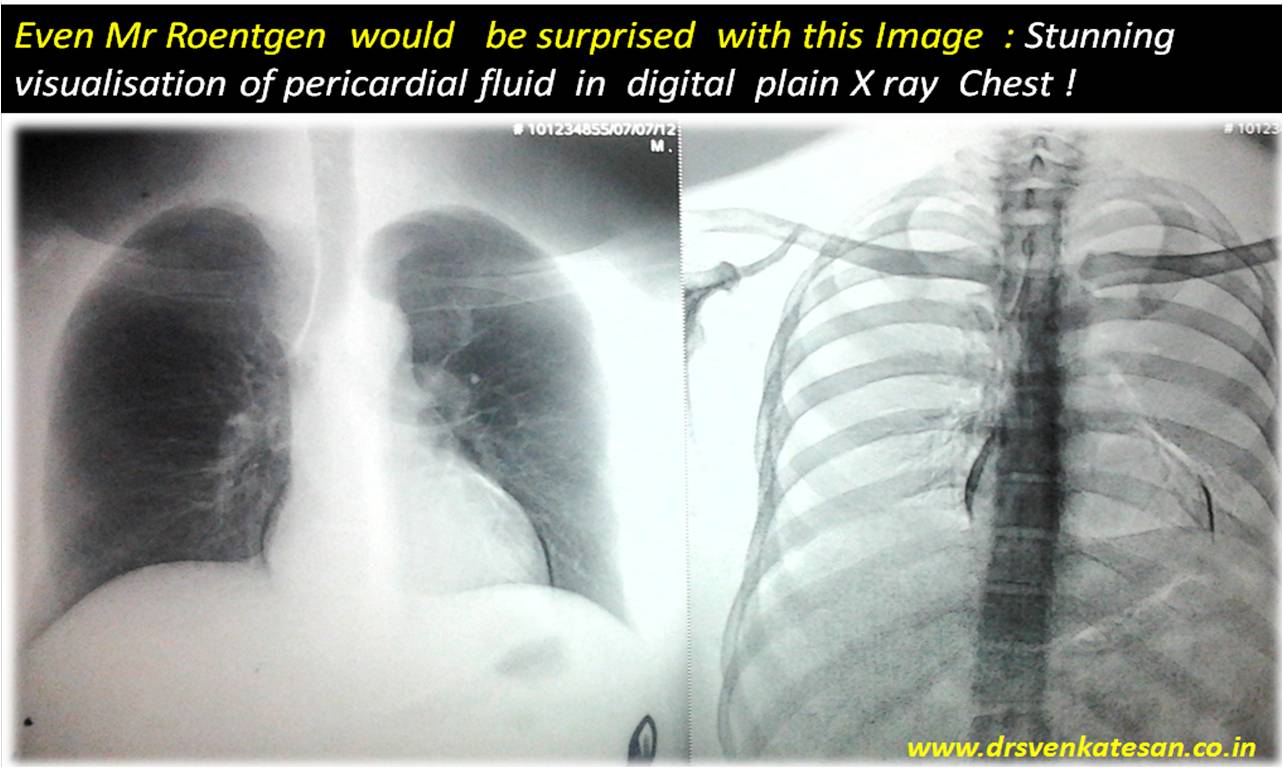

How did the pericardial fluid became radio opaque ?

This X-Ray surprised me . . . may be . . . Mr Roentgen as well !